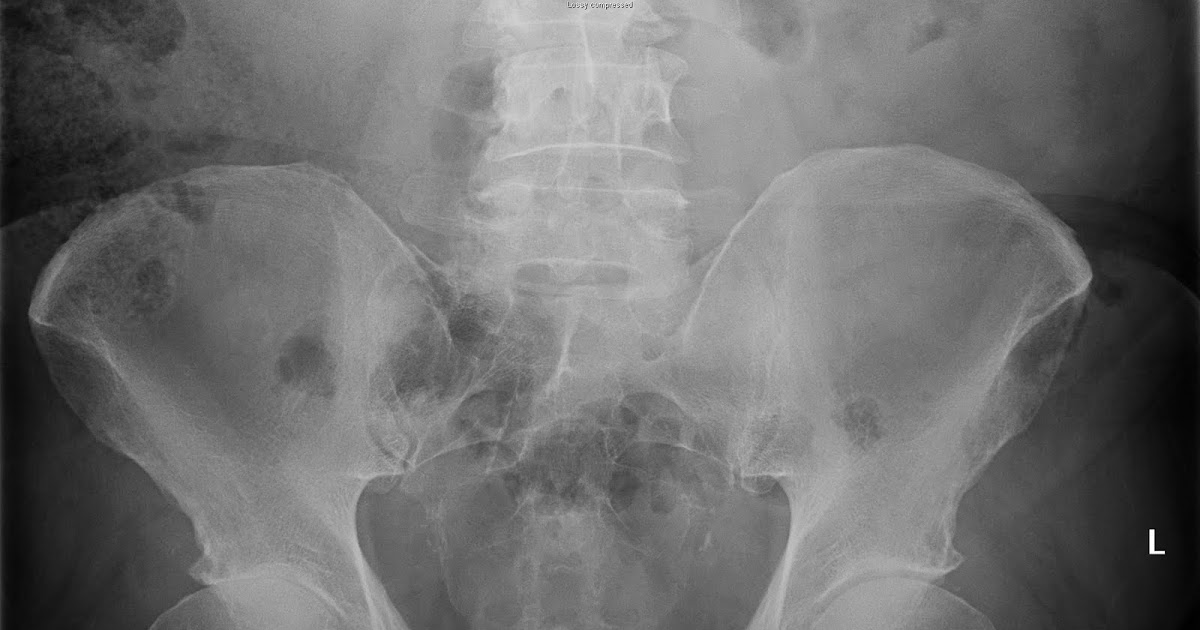

Plain x ray of pelvis showing ''pistol grip deformity'' of both... Download Scientific Diagram What Is Pistol Grip Deformity Pistol grip deformity (pgd) may be the main factor in femoroacetabular impingement development. This study aimed to clarify the. The overgrown or misshapen bone contacts the cartilage that lines the hip. The overgrown or misshapen bone contacts the cartilage that lines the hip socket, and can cause it to peel away from the bone in the socket. The overgrown or. What Is Pistol Grip Deformity.

A/P Xrays of the pelvis showing a bilateral pistol grip deformity of... Download Scientific What Is Pistol Grip Deformity The overgrown or misshapen bone contacts the cartilage that lines the hip. This study aimed to clarify the. Femoroacetabular impingement (fai) is the abnormal contact between the femur and acetabulum which may lead to labral damage, various degrees of chondral injury and. The overgrown or misshapen bone contacts the cartilage that lines the hip socket, and can cause it to. What Is Pistol Grip Deformity.

Plain x ray of pelvis showing ''pistol grip deformity'' of both... Download Scientific Diagram What Is Pistol Grip Deformity The overgrown or misshapen bone contacts the cartilage that lines the hip socket, and can cause it to peel away from the bone in the socket. The overgrown or misshapen bone contacts the cartilage that. By studying a pediatric population, we were able to characterize the temporality between cam morphology (occurring 1st) and joint. This study aimed to clarify the.. What Is Pistol Grip Deformity.

A/P Xrays of the pelvis showing a bilateral pistol grip deformity of... Download Scientific What Is Pistol Grip Deformity The overgrown or misshapen bone contacts the cartilage that lines the hip. The overgrown or misshapen bone contacts the cartilage that lines the hip socket, and can cause it to peel away from the bone in the socket. Pistol grip deformity (pgd) may be the main factor in femoroacetabular impingement development. This study aimed to clarify the. Femoroacetabular impingement (fai). What Is Pistol Grip Deformity.